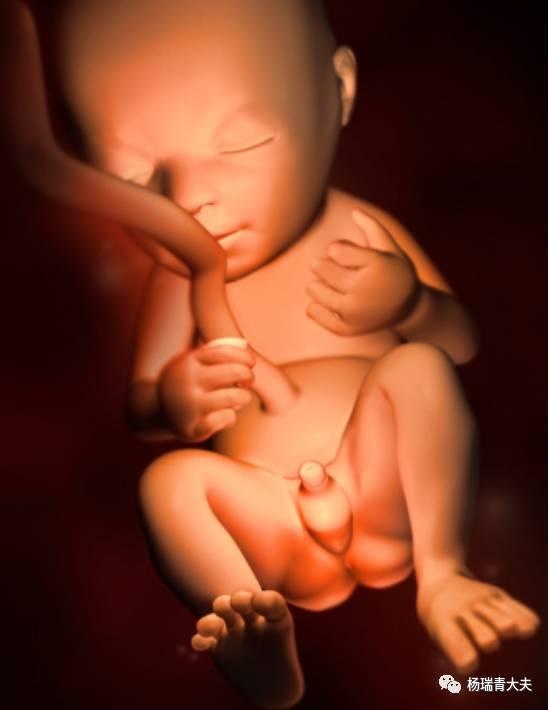

“宫内5D电影”其实就是通过5彩超实时动态地显示胎儿在子宫内的情况,先来组静态图,虽然是静态,但看得更清楚,图片也足够惟妙惟肖,必定能激发起您的想象力哦!

再看看这张动态图片,通过5D彩超,孕妈可以看到胎宝在腹中微笑、吮手指、踢腿、伸懒腰、打哈欠,通过它可以捕捉到宝宝在母体内的一举一动